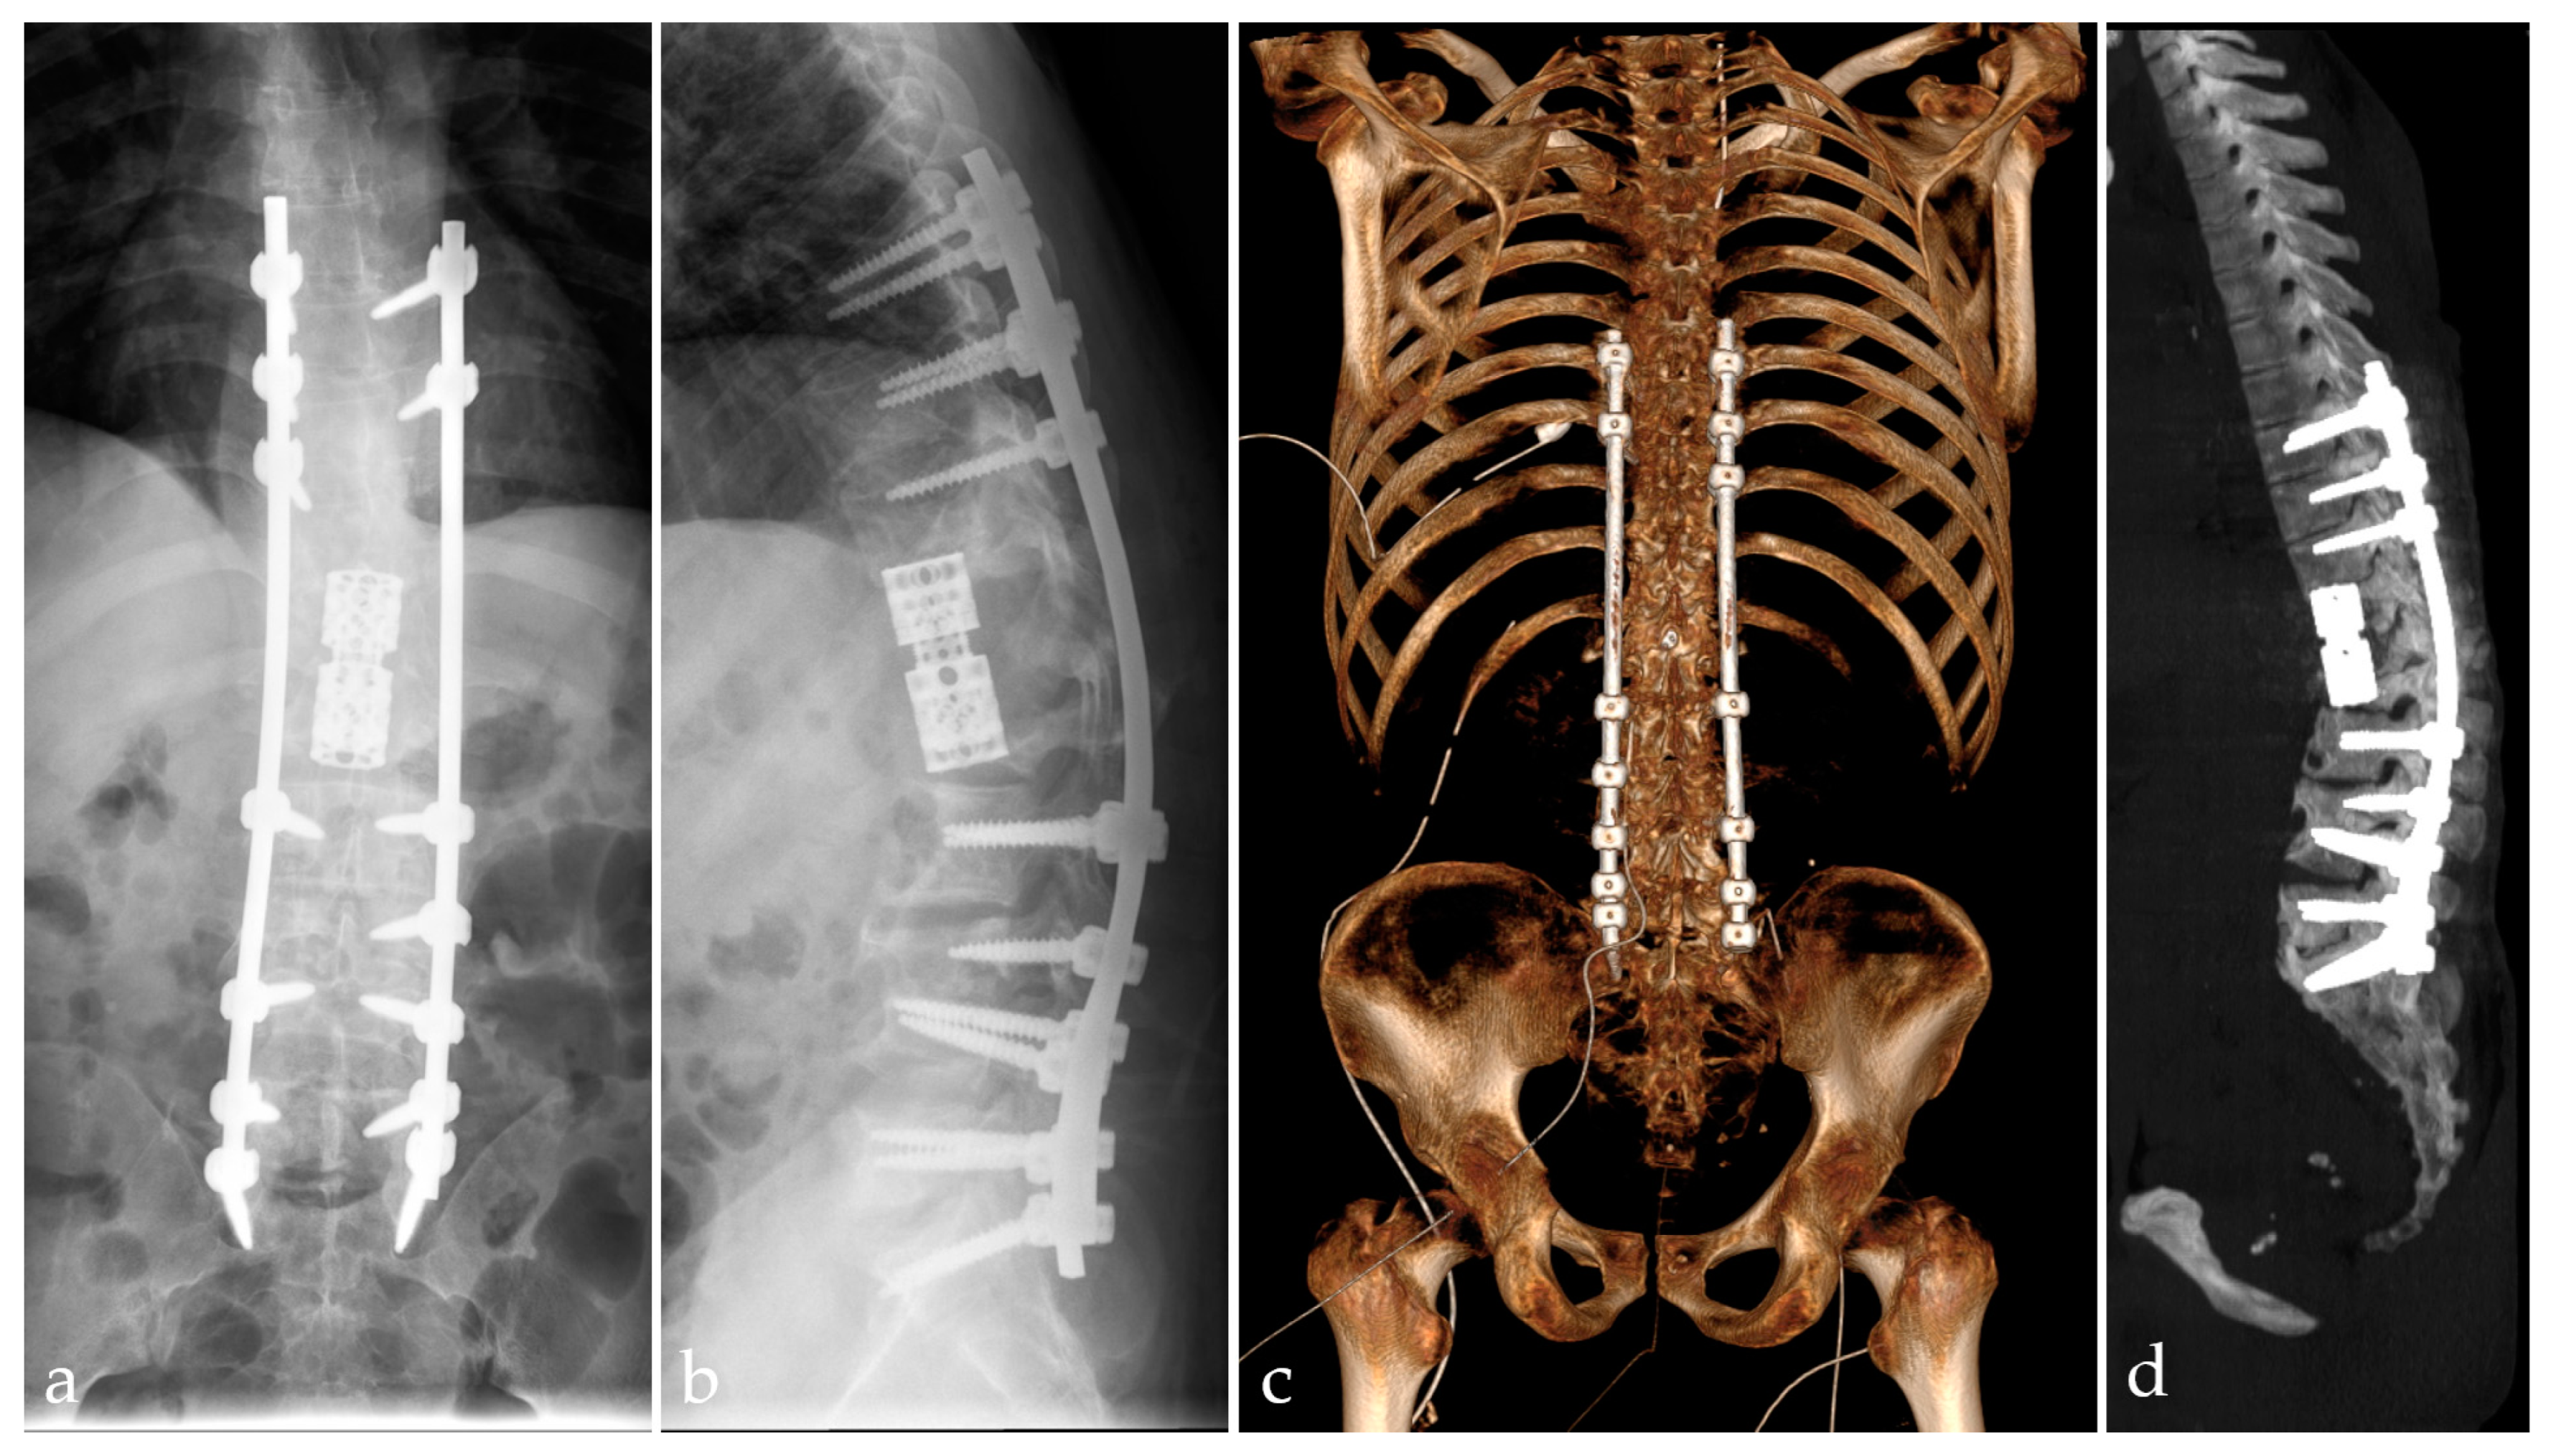

2.5. Management and Surgical Procedures